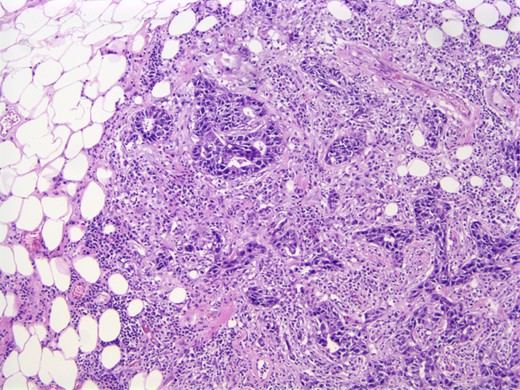

A computed tomographic (CT) scan of her chest with contrast revealed moderate right axillary lymphadenopathy and a lesion in the upper outer quadrant of the right breast measuring 1.3 × 1.2 cm (Fig. 1). A positron emission tomography (PET) scan showed a small intense focus on the right lateral breast consistent with carcinoma, significant right axillary lymphadenopathy and intense fluorodeoxyglucose hypermetabolic activity consistent with metastatic spread. Additionally, enlarged lymph nodes extending along the upper chest wall just inferior to the subclavian vessels and posterior to the pectoralis muscles were seen. A needle biopsy of the mass revealed an extensive involvement of poorly differentiated infiltrating carcinoma (Fig. 2). The tumor showed large nuclei with eosinophilic cytoplasm and prominent nucleoli consistent with apocrine differentiation (Fig. 3). There was a significant inflammatory response to the infiltrating tumor noted. No lymphovascular invasion was identified within the core biopsies. The specimen was estrogen and PR negative as well as HER-2/neu negative.

Photomicrograph: large nuclei with eosinophilic cytoplasm and prominent nucleoli consistent with apocrine differentiation.